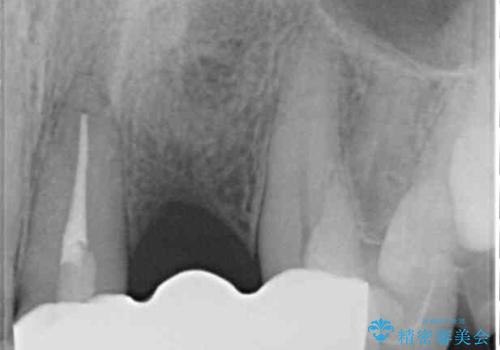

- 前歯が折れてしまい、ブリッジによる補綴治療を希望して来院された患者様です。

折れている前歯は抜歯をし、痩せてしまう歯肉は移植術により増大させることで審美面を回復した後、オールセラミックブリッジにて補綴することとしました。

インプラントかブリッジか悩むところでしたが、既に治療されている前歯のクラウン周りの変色が気になっていたため、ブリッジにより色調を合わせたオールセラミックを装着することを選択しました。